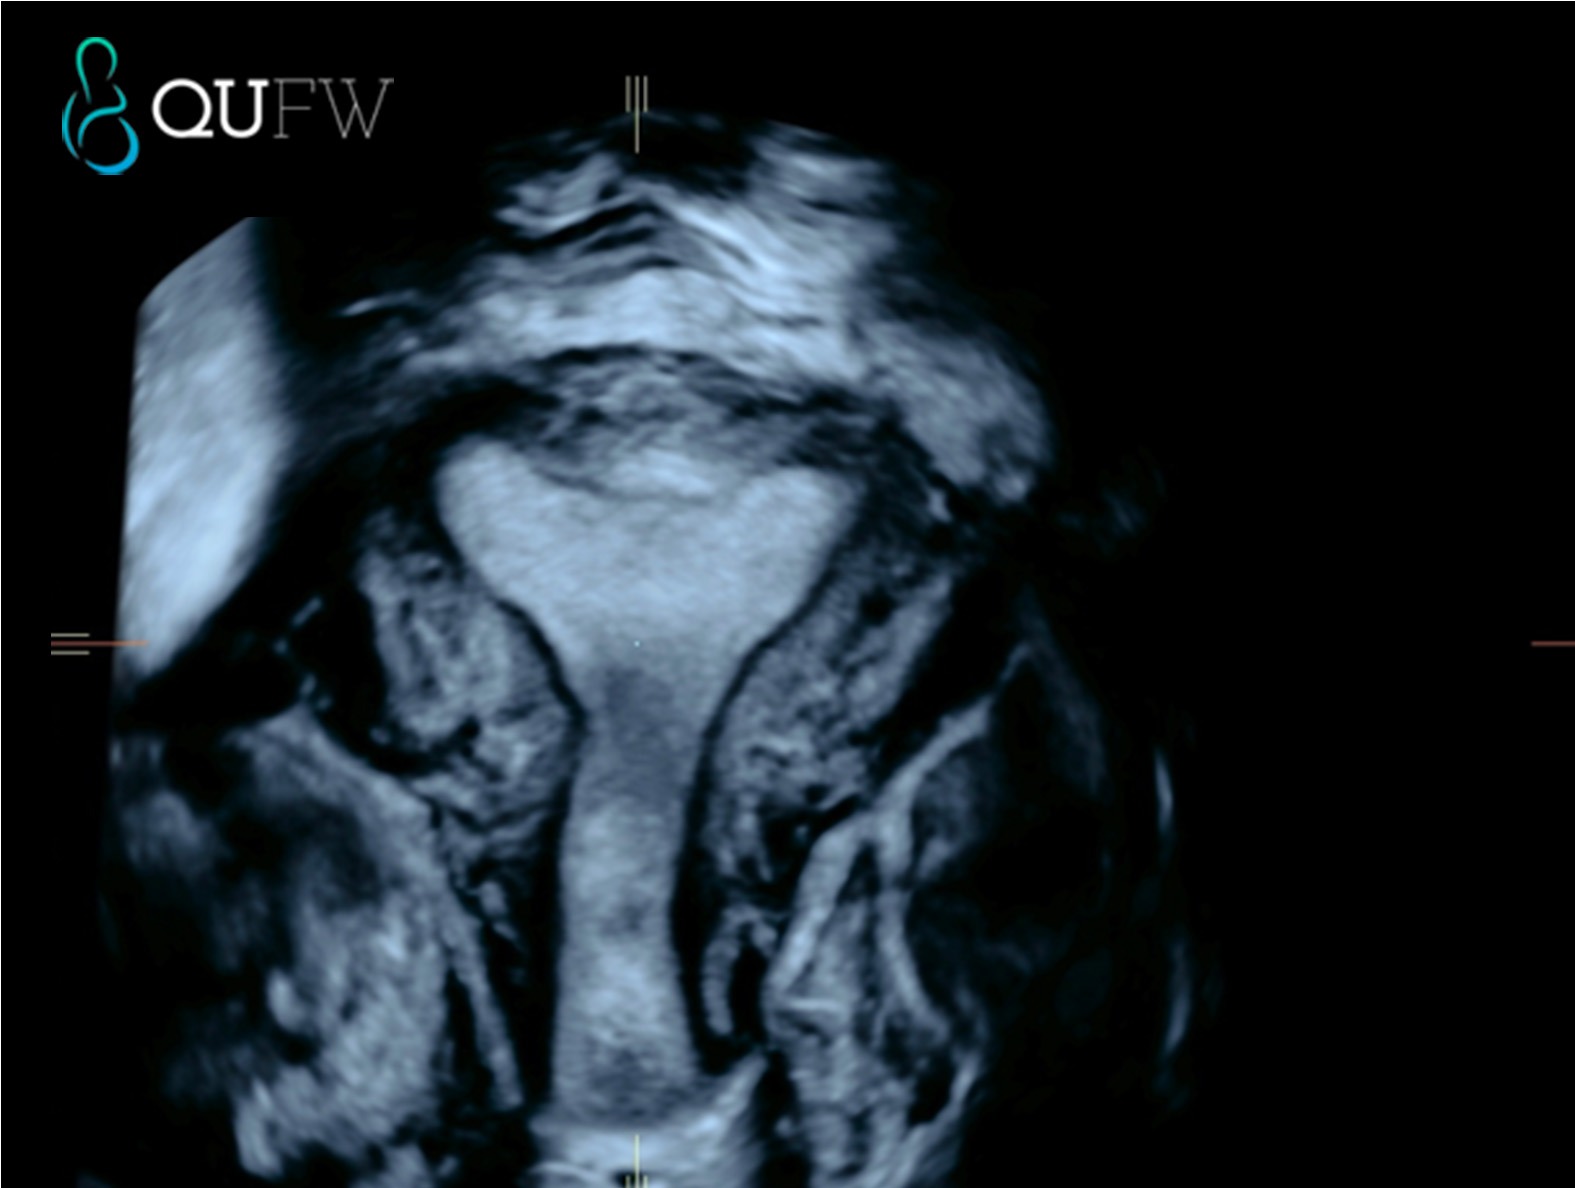

- Uterus: The ultrasound scan examines the size, position and shape of the uterus such as a septate or bicornuate uterus. It evaluates the endometrium (the lining of the uterus) for thickness and abnormalities, which can be important in evaluating causes of fertility issues. The ultrasound can also detect fibroids (benign tumours in the uterine muscle) or polyps (growths in the endometrium). 3D/4D ultrasound techniques are routinely utilised to demonstrate the uterus in the plane that we all recognise from the textbooks.

3D reconstructed coronal image of the uterus